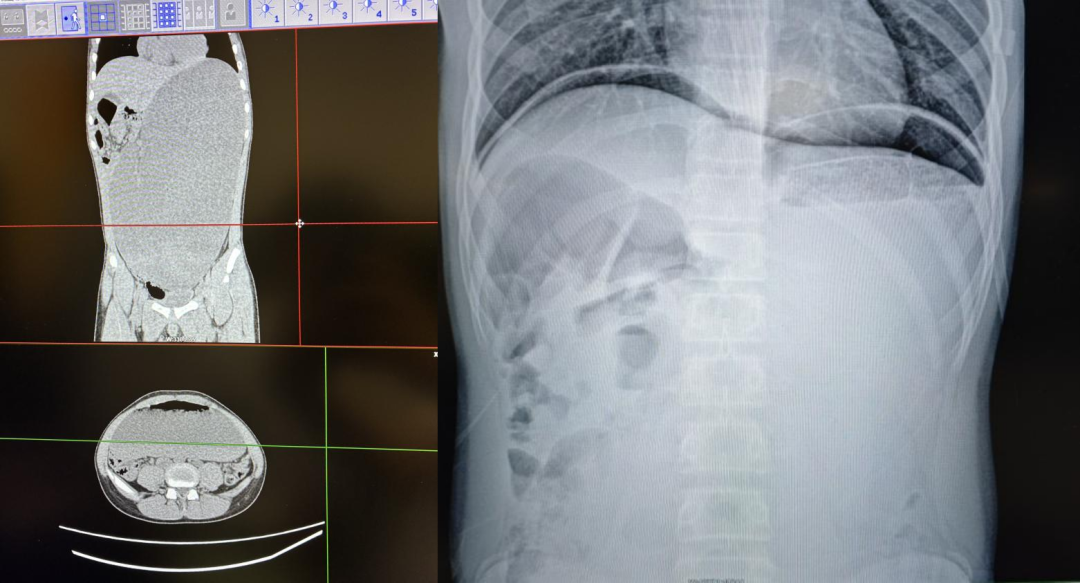

立位腹平片提示中腹部密实,该院综合外科张向宁副主任医师紧急会诊后,高度怀疑存在“空腔脏器穿孔”可能,随即启动急诊预案,完善腹部CT检查。CT结果令人震惊:胃腔显著扩大,内部充满大量胃内容物。在积极进行胃肠减压、抗感染、扩容抗休克治疗的同时,患儿突然出现难以忍受的剧烈腹痛。复查立位腹平片,腹腔内出现了明确的游离气体——这意味着“消化道穿孔”的诊断已确凿无疑,病情万分危急,必须立即手术!